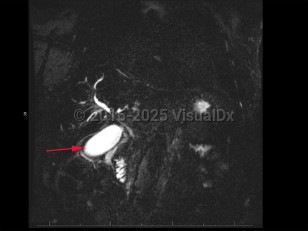

Imaging Studies image of Cholangiocarcinoma - imageId=8368519. Click to open in gallery.  caption: '<span>MCRP demonstrates peripheral and central enhancement consistent with cholangiocarcinoma.</span>'

MCRP demonstrates peripheral and central enhancement consistent with cholangiocarcinoma.